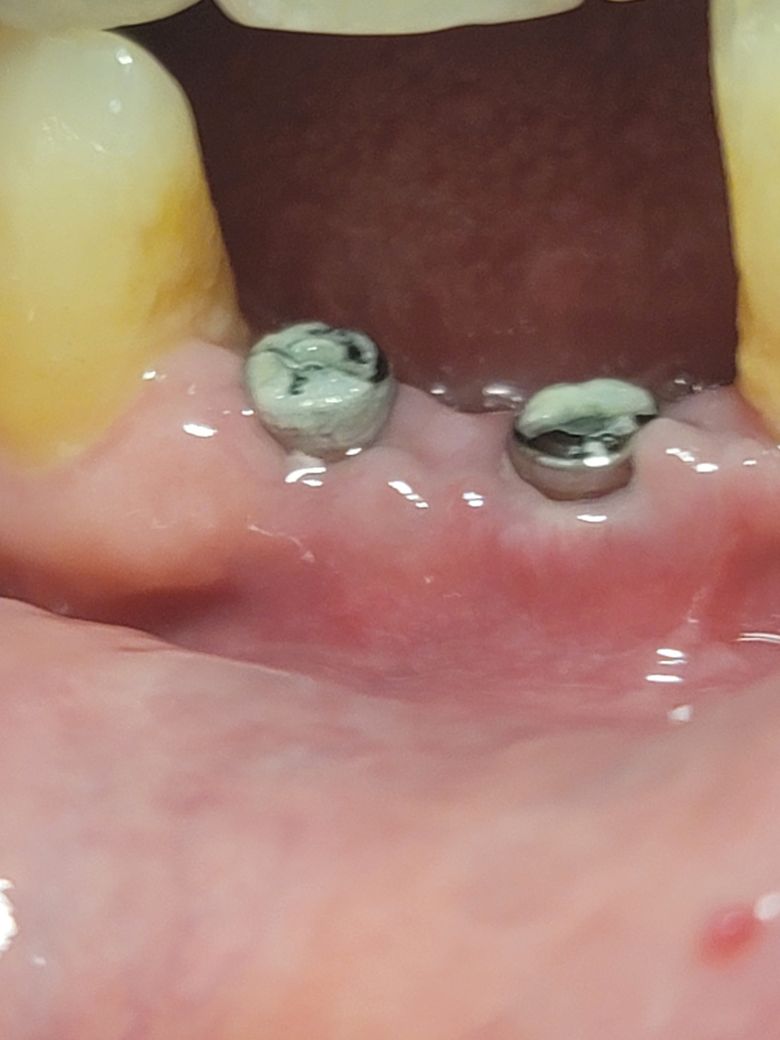

1) 현재 수술 후, 만 16일이 지난 상태인데, 힐링 어버트먼트가 육안으로 많이 보입니다. 수술 직후에는 힐링 어버트먼트가 거의 보이지 않았는데, 지금은 힐링 어버트먼트가 너무 노출되어 잇몸뼈 침식이 일어나는건가 걱정이 됩니다. 한마디로, 힘들게 인공 잇몸뼈로 잇몸뼈 성형을 했는데, 모조리 녹아내린건가 걱정이 됩니다. 아니면, 수술 후, 부어있는 잇몸에 붓기가 빠지면서 자연스럽게 노출된걸로 봐야 하나요? 치과에 빨리 예약하고 내원해서 상태를 점검 받아야 할까요?

2) 수술 전후를 비교해보면.... 사진 기준으로 좌측은 잇몸이 살짝 올라온 것 같고, 우측은 아쉽게도 큰 변화는 없는거 같구요... 뼈이식으로 잇몸이 조금 재생되었다고 판단해도 될까요?

3) 잇몸뼈 재생관련: 제가 이해하기로는 인공잇몸뼈를 이식하면, 제 잇몸뼈가 인공잇몸뼈를 양분삼아(?) 재생한다고 알고 있습니다. 그러나, 제 나이를 고려하면, 이식한 인공잇몸뼈 이상으로 잇몸이 재생하기는 어렵다고 보면 되나요? 구체적으로 현재 제 상태에서 힐링어버트먼트 위로 잇몸이 덮을 정도로, 잇몸뼈가 자라기는 힘들겠죠?

4) 우측의 경우에 안쪽에 힐링어버트먼트를 감싸는 잇몸도 부족해보이고, 임플란트가 비쳐보이는 것 같습니다. 너무 좁은 앞니에 무리하게 임플란트를 한건 아닌지 걱정이 됩니다. 앞니 임플란트 부작용이라며, 잇몸뼈가 녹아서, 임플란트가 노출된 사진들이 많던데 덜컥 겁이 납니다. 어떻게 보시나요?

• 3번 째 사진

• 4번 째 사진